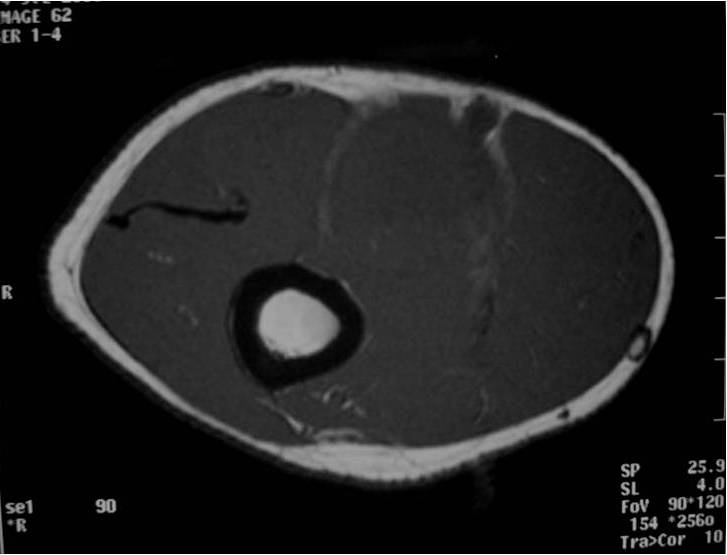

MRI appearance (Fig. 1 – 4)

• Intermuscular mass closely related to a neurovascular bundle with a distinct margin surrounded by rim of fat (split fat sign)

• Fusiform, elongated cigar shaped mass

• Nerve: Tubular structure visualized entering and exiting the mass (may be difficult to see with small lesions or lesions of the trunk or retroperitoneum) (Fig. 2 & 4)

• T1: Isointense to muscle; Variable enhancement with gado

Fig. 1-4 MR image demonstrates a 5 cm intermuscular mass in the anterior compartment of the arm arising along the course of the neurovascular structures. Isointense to muscle on T1W image and heterogeneous high signal on T2W with low signal in the central area (Antoni A) and peripheral high signal (Antoni B), known as “Target Sign”. Coronal image shows a structure entering and exiting the mass (median nerve).